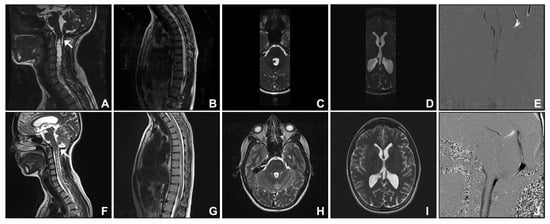

3.1. Group One. Post-Traumatic Cranio-Cervical Junction Arachnoiditis and Syringomyelia

3.2. Group Two. Dural Band

3.3. Group Three. Spontaneous Intracranial Hypotension

3.4. Group Four. Idiopathic Intracranial Hypertension

3.5. Group Five. Cysts: Arachnoid, Choroid Plexus, and Cerebellum